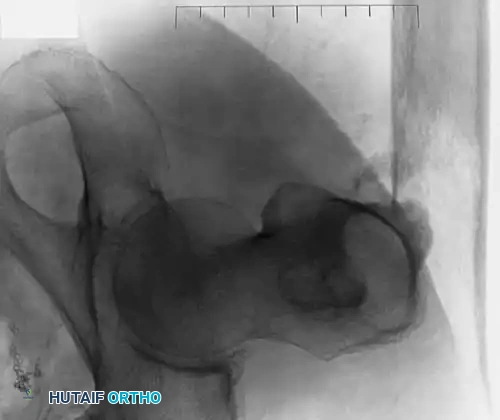

Fig. 22-19: (A) Anteroposterior view of the left hip of a 50-year-old woman with a history of breast cancer, disease-free for 2 years. A lytic lesion is seen in the femoral neck. Although the most likely diagnosis is metastatic carcinoma, a biopsy must be performed. This lesion proved to be a malignant fibrous histiocytoma (primary sarcoma). (B) Anteroposterior view after wide resection and endoprosthetic reconstruction. Prophylactic fixation of this presumed metastasis would have severely compromised her oncologic outcome.